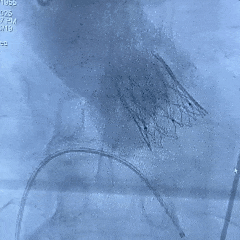

手术过程

左冠造影检查

20mm球囊扩张,无腰无漏,球囊轻微滑动

TF23瓣膜0位初始释放

瓣膜第一次展开造影评估,位置偏浅,回收调整

第二次释放造影评估

瓣膜深度可,展开良好,无瓣周漏

瓣膜解锁后造影评估

瓣膜深度合适形态良好,冠脉灌注良好,无瓣周漏

最终多角度观察瓣膜形态,瓣膜展开良好

超声测量流速1.5m/s,手术结束